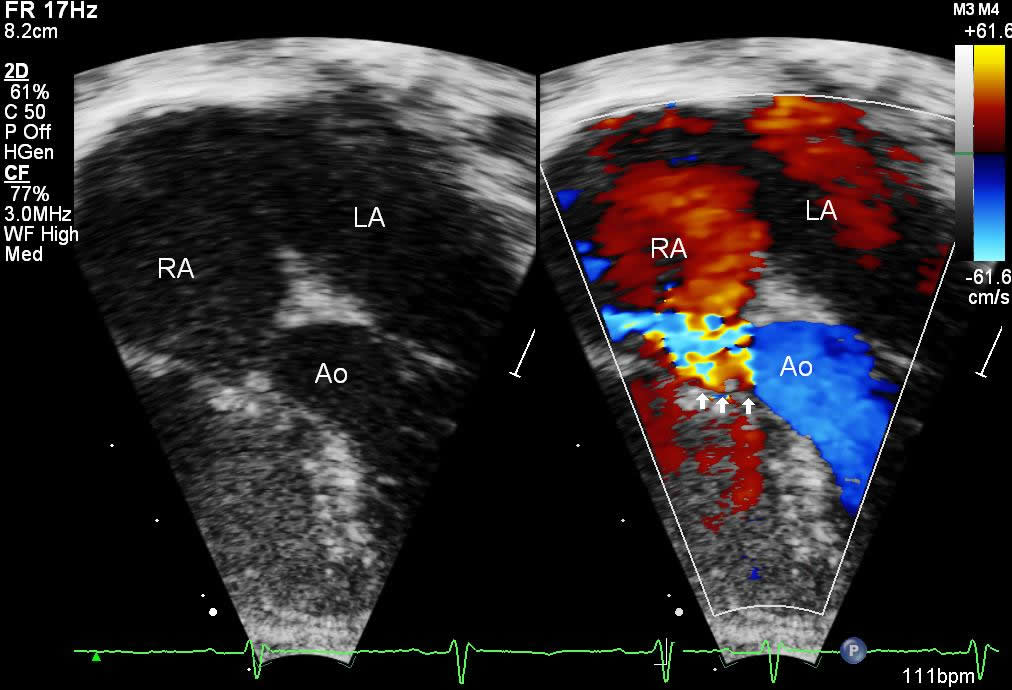

All patients were diagnosed with echocardiography. Figure 6 shows a 4-chamber view where the color Doppler jet travels from the left ventricle into the right atrium. Figure 7 demonstrates the Doppler envelope. The maximum peak instantaneous gradient in this patient was 150 mm Hg. This high Doppler gradient is one of the hallmarks of the Gerbode ventriculo-atrial defect because of the difference between the left ventricular systolic pressure and the low right atrial pressure. The echocardiogram gradient ranged from 65 to 150 mm Hg, with a mean echo gradient of 95 mm Hg. Echocardiography confirmed a dilated right atrium in all patients.